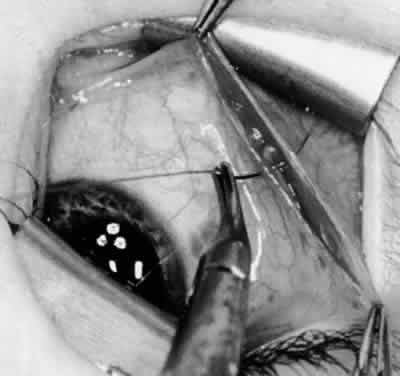

Fig. 11. Sutures are placed into the insertion of the inferior oblique muscle before it is sectioned from the globe for the recession procedure.

Fig. 12. An Aebli scissor is placed beneath the inferior oblique muscle insertion before it is sectioned from the globe.

Fig. 13. The inferior oblique muscle is sectioned from the globe. A preplaced 6-0 Vicryl suture is attached to the insertion.